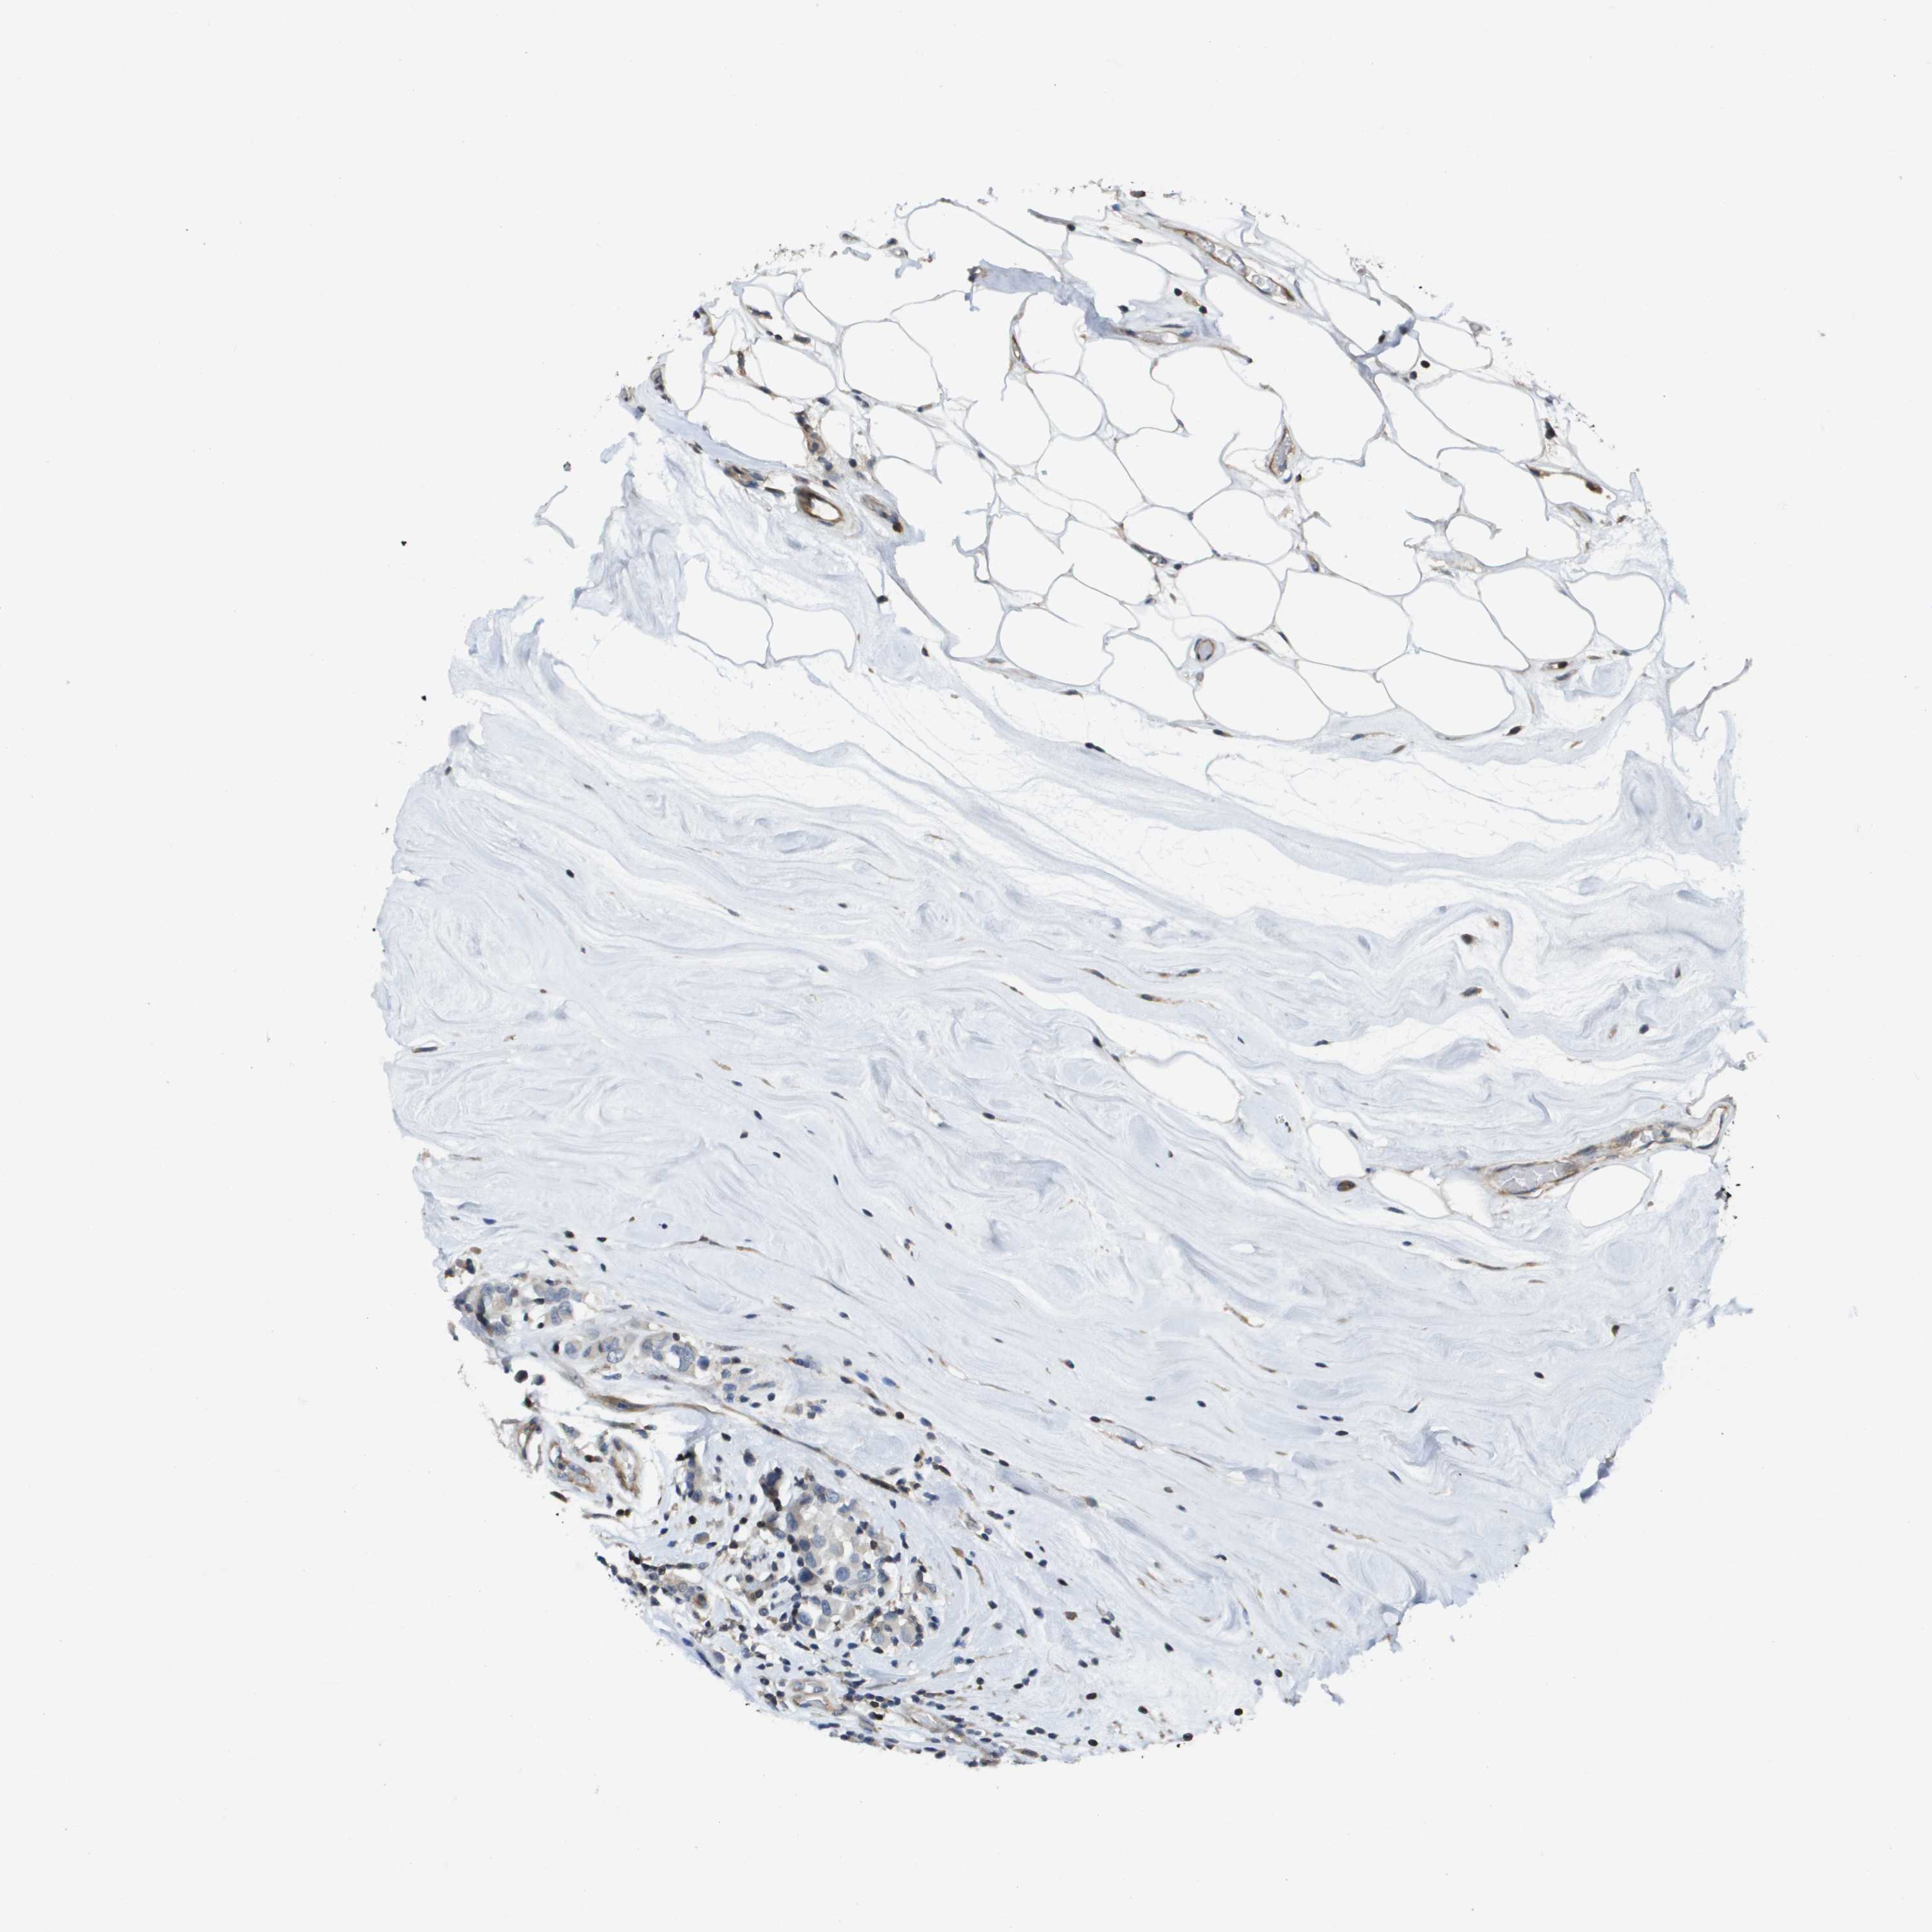

BRCA TCGA BRCA VALIDATION PROTEIN EXPRESSION

ANTIBODIES

AND

VALIDATION